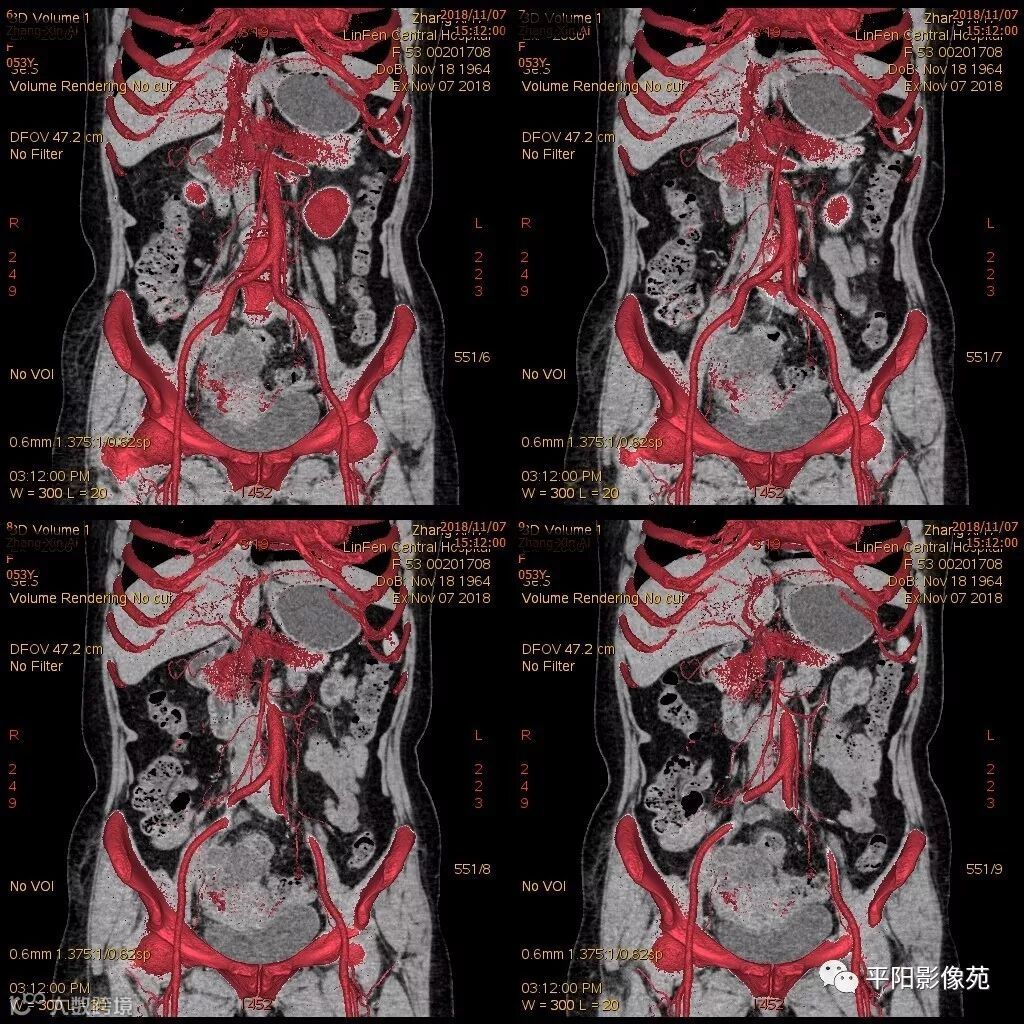

影像特点

右附件区薄壁囊性病变,壁明显强化,边界不清,供血动脉源自子宫动脉,且局部动脉血管增多;其内侧可见卵圆形无强化囊性病灶。

附件区病变多见于卵巢,以囊性为主的病灶多为卵巢囊肿、粘液/浆液性囊腺瘤、皮样囊肿等,这些病灶都具有鲜明瘤体结构,且壁强化多为轻-中度,供血动脉多源自卵巢动脉;而本例患者右附件区薄壁囊性病灶,多位置观察形态为迂曲管状,且壁有明显延迟强化,供血动脉源自子宫动脉,较对侧血管丰富,故而考虑源自输卵管或子宫病变,但子宫发生的薄壁囊性病变较少,多见于子宫肌瘤囊变,完全囊变者少见,且形态轮廓与肌瘤相同为球形故而排除,结合患者腹痛前有感冒病史,且有压痛,因此考虑输卵管积脓可能。其内侧无强化囊性肿块,考虑卵巢囊肿可能。

主要与卵巢囊肿伴感染、皮样囊肿、卵巢囊腺瘤等鉴别,当病变表现相似时,可根据供血动脉以兹鉴别,卵巢病灶为卵巢动脉供血,其自腹主动脉,输卵管病变多由输卵管动脉供血,源自髂内动脉→子宫动脉→输卵管动脉。